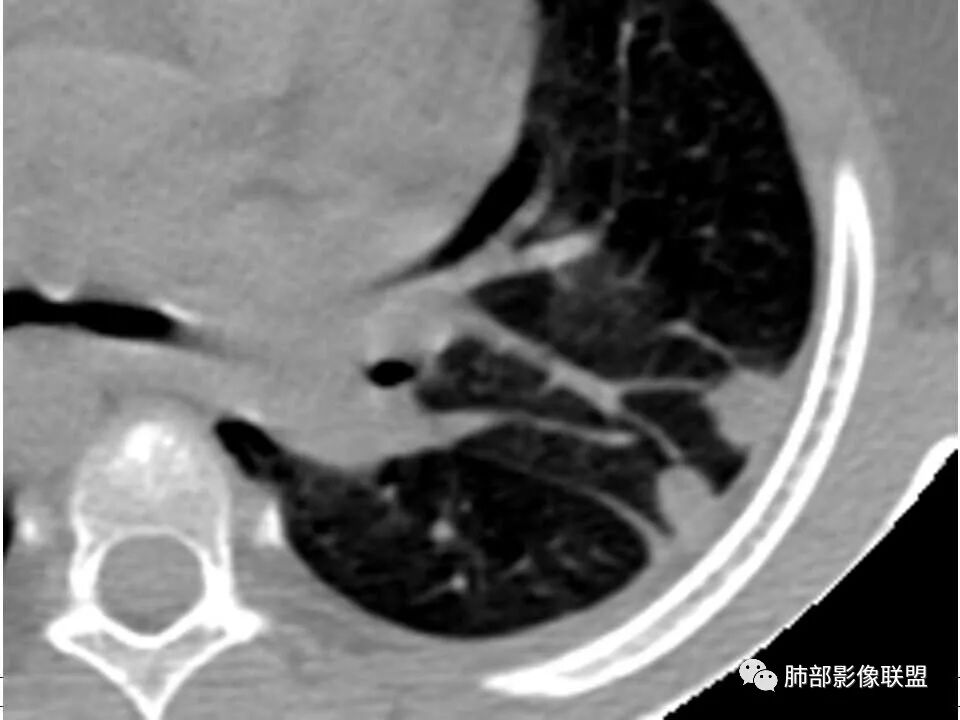

患者儿童,因右下肢疼痛伴肿胀14天就诊。病程中有发热及伴随症状。膝关节MRI提示右侧膝关节及右髌骨髁异常信号影,右膝髌上囊及关节腔内少量积液。胸部CT:双肺胸膜下多发结节影,部分结节空洞形成,且结节周围可见血管集束征。综合考虑血源性脓毒性肺栓塞、坏死性肺炎。右侧骨髓炎、血播性金葡菌肺炎,鉴别其他特殊感染及血管炎。

胸部ct:双肺多发空洞,结节,外带下叶为主,空洞内外光滑,有血管滋养征,综合病史及影像考虑脓毒性肺栓塞,结合病史,金葡可能性大。

小儿,急性起病,下肢疼痛,mr提示骨髓水肿,临床化验炎性指标高,考虑金葡菌骨髓炎,双肺多发结节,以血管支气管束及胸膜下分布为主,部分结节近端与血管相连,部分结节可见空腔,内壁光整,部分囊腔有张力,考虑骨髓炎并肺内血播感染,金葡?

2.双肺多发片影,随机分布,多空洞或囊腔,胸膜下多楔形影,气道未见受累等等符合脓毒血症影像学表现,尤其是金葡。